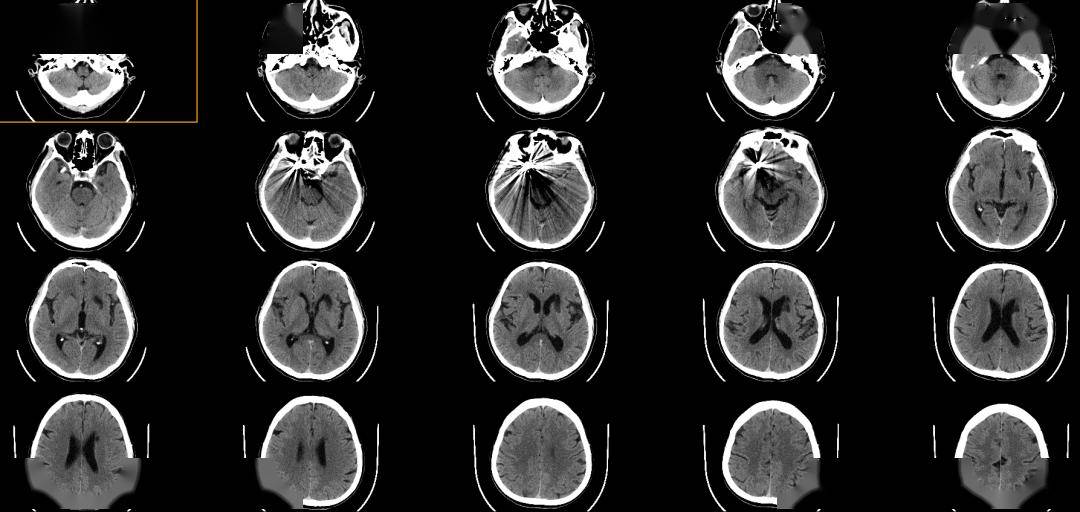

术后CT